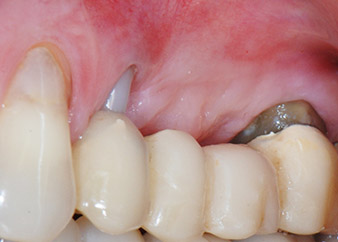

Figures 17 and 18 show the clinical result two months after the surgery. Tooth 24 exhibited reduced mobility of Miller class 1, and the soft tissues were free of inflammation. Probing was avoided at this point of time to prevent reinfection and to avoid violating the epithelial attachment. A control visit was scheduled for reentry and placement of healing abutments, six months after the insertion of the implants.

Two months after the surgery, the patient was pain-free.

Fig. 17: Two months after the surgery, the patient was pain-free and the area was free of inflammation.

after the surgery

Fig. 18: Tooth 24 now showed less mobility.